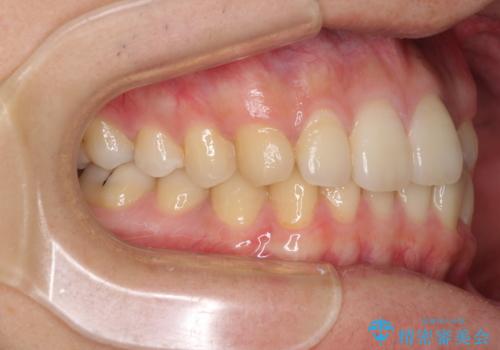

前歯のクロスバイトと抜歯が必要な奥歯の虫歯 インビザラインとインプラント治療

- 前歯のクロスバイトと、大学生のころから放置している虫歯を気にして来院された患者様です。

マウスピースでの矯正治療を希望されていましたが、前歯のクロスバイトは不十分な仕上がりや歯髄壊死などのリスクが高くなるため、術前にワイヤーで大まかに整えてからインビザラインにて矯正治療を行うこととしました。

奥歯の虫歯は抜歯が必要であったので、矯正治療前に抜歯をし、矯正治療と並行してインプラントによる補綴治療を行うこととしました。